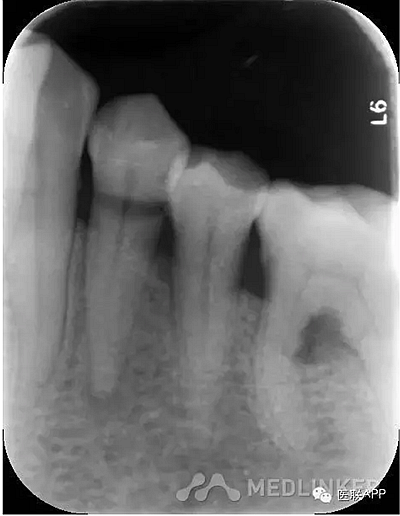

34頰側(cè)楔狀缺損達(dá)髓腔,可探及穿髓孔,探痛(-),叩痛(+),松動(dòng)I度。

X線示:34根尖周小面積低密度影。

診斷:34慢性根尖周炎